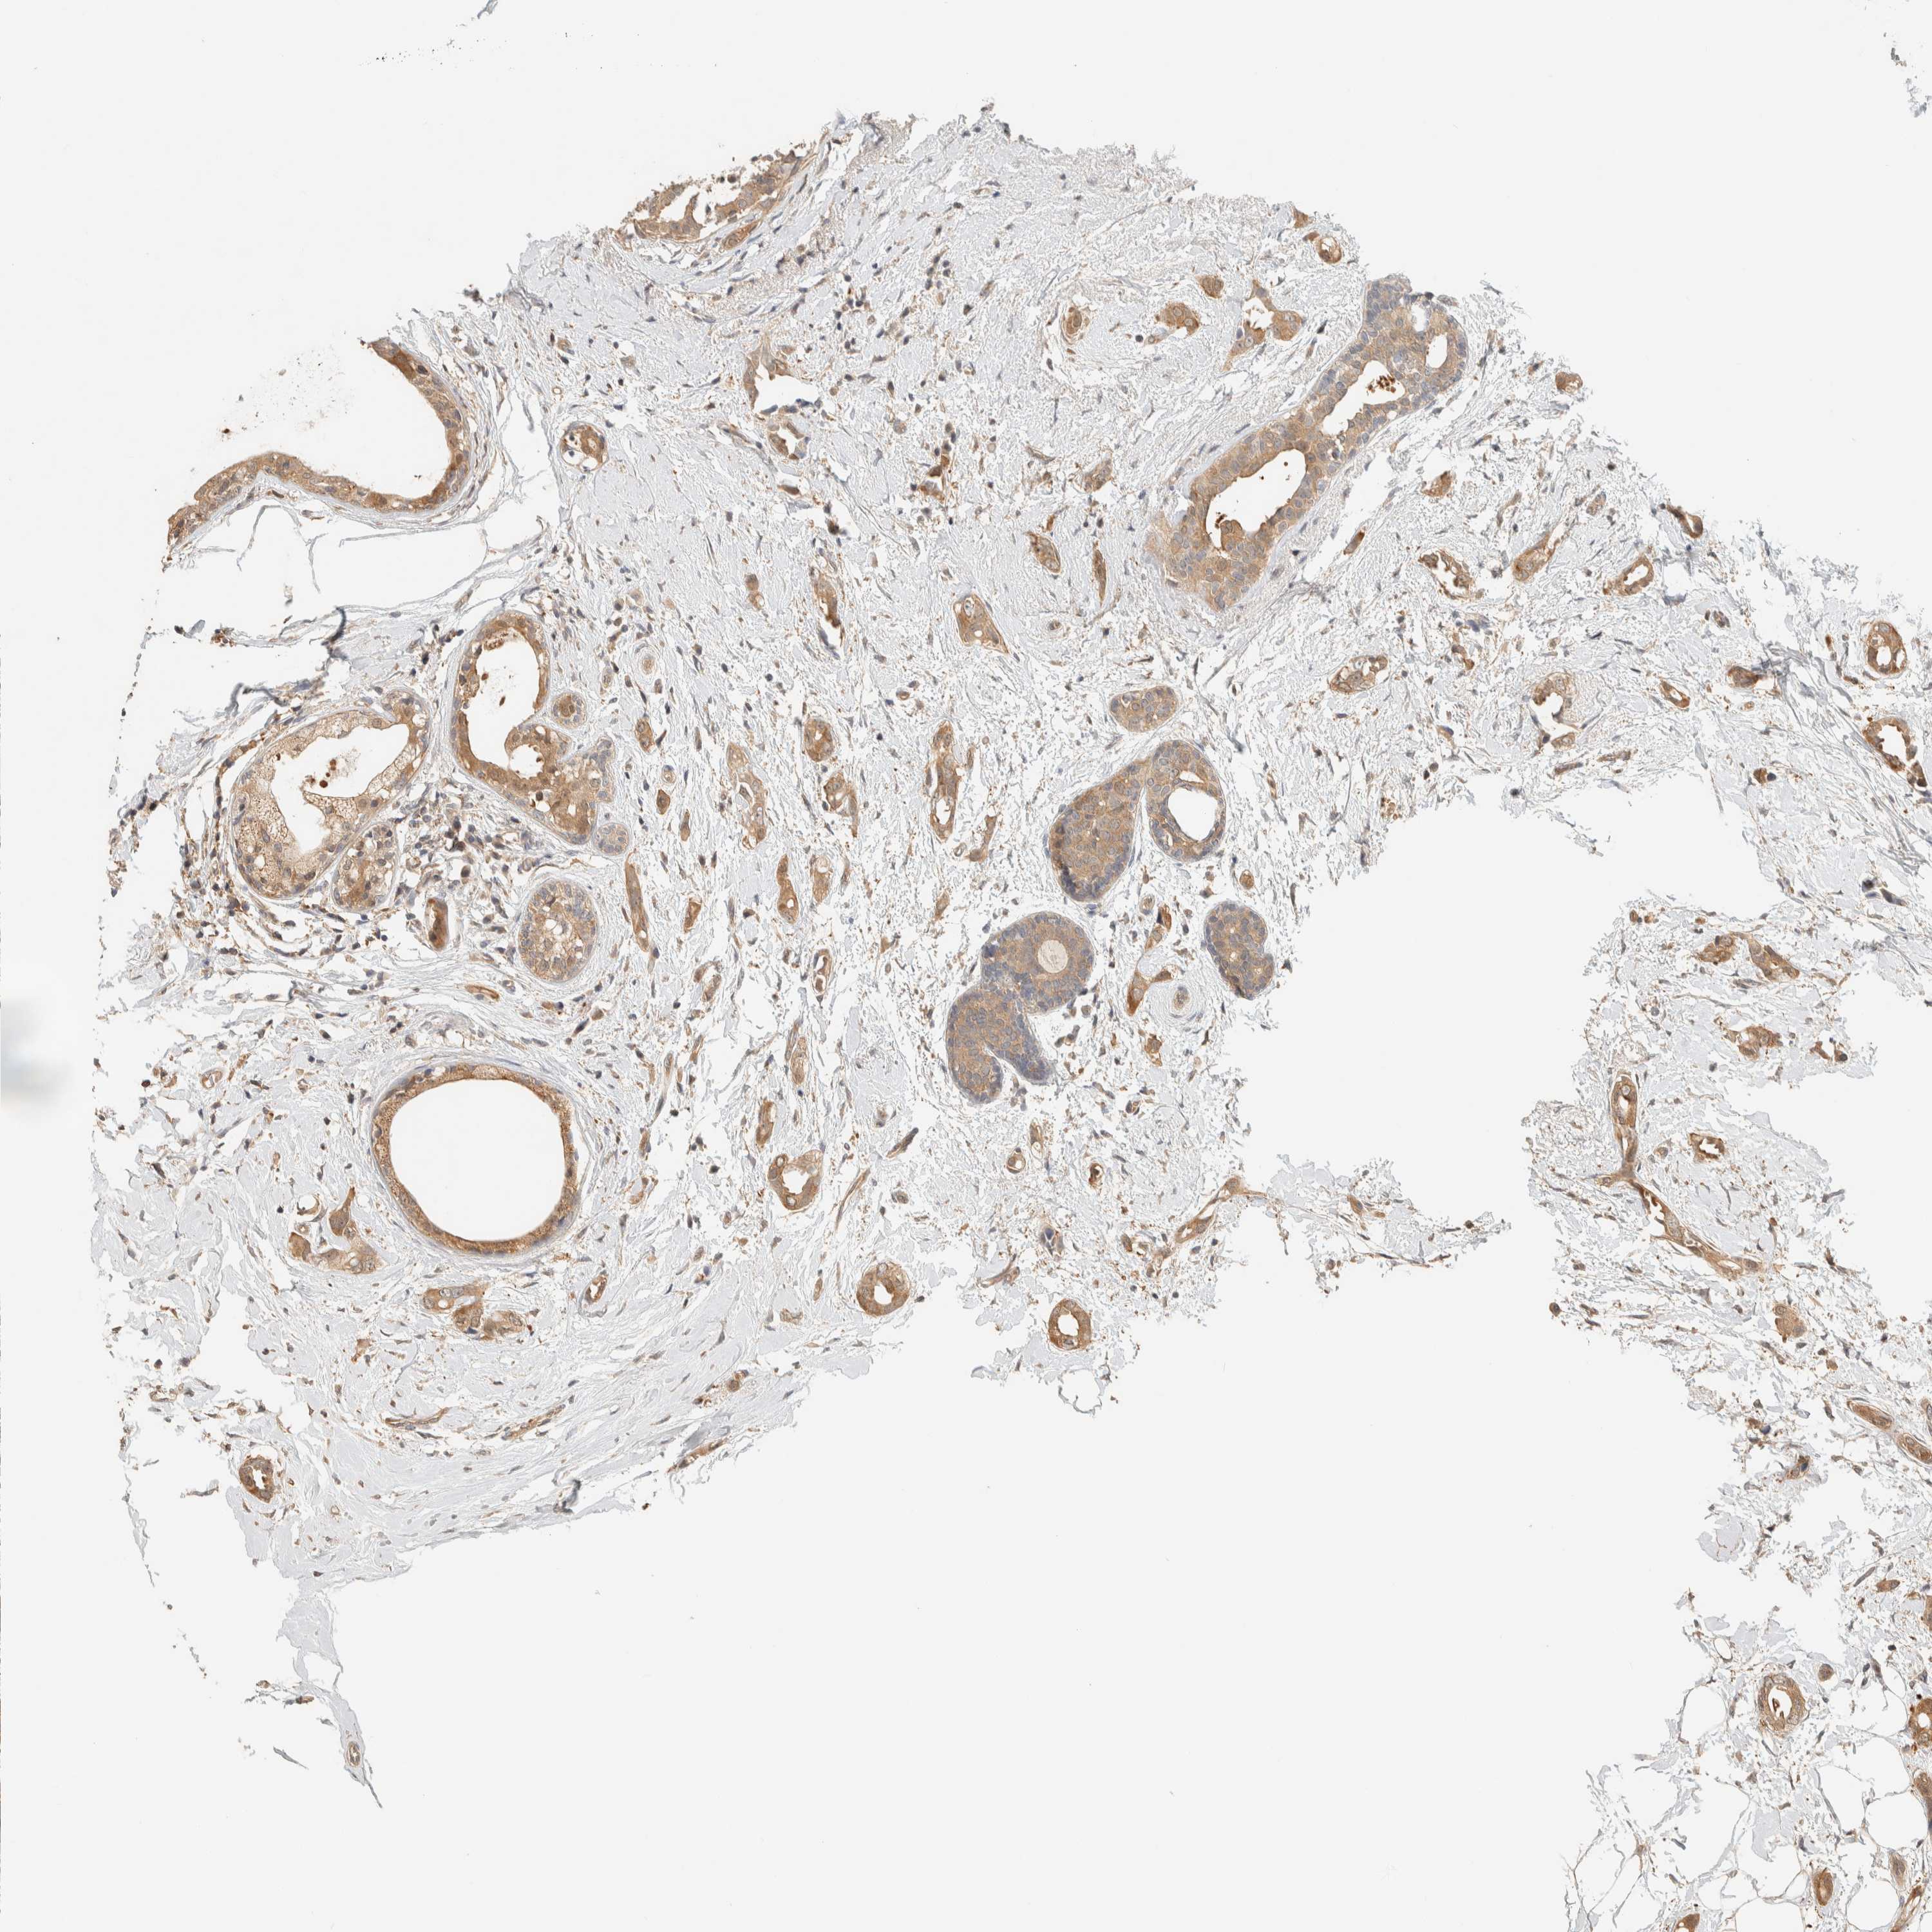

BRCA TCGA BRCA VALIDATION PROTEIN EXPRESSION